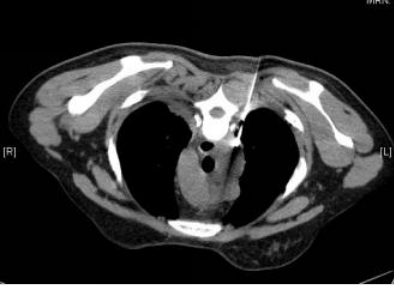

患者入住RICU后监测生命体征,予以碳酸氢钠+奥硝唑注射液胸腔冲洗;予以哌拉西林他唑巴坦+奥硝唑静滴抗感染,同时给予氧疗、补液、护肝等各脏器功能支持治疗。患者严重营养不良,吞咽困难、食欲差,恶心呕吐明显,遂给予肠内联合肠外营养支持。经治疗患者仍高热,4月3日给予经皮纵隔穿刺(图2),抽出约10 ml脓性液体。体温恢复正常3天后再次高热,PPD试验硬结直径小于5 mm,多次胸水抗酸染色未查到抗酸杆菌,多次胸水、血、穿刺液培养均阴性。调整抗感染方案为利奈唑胺+头孢噻利,仍有反复高热,调整抗生素为利奈唑胺+比阿培南,4月12日复查胸部CT考虑可能纵隔脓肿未引流尽,且左下肺积液有包裹(图3),建议患者外科行胸腔镜治疗,患者家属拒绝,故于4月17日行CT引导下经皮胸腔脓肿穿刺抽液,抽出约30 ml暗红色液体,患者体温降至38℃左右,拔除胸腔闭式引流管。患者体温逐渐恢复正常,5月7日再次予左侧包裹脓腔行B超引导下穿刺抽液,抽出约60 ml淡红色液体。5月16日出院后口服抗生素2周。6月14日复查胸部CT吸收理想(图4)。注:A、B、C为右侧颈部、纵隔脓肿及左侧胸腔积液较前吸收,D为左下肺仍有包裹性积液图4 复查胸部CT病灶基本吸收(2012-06-14)